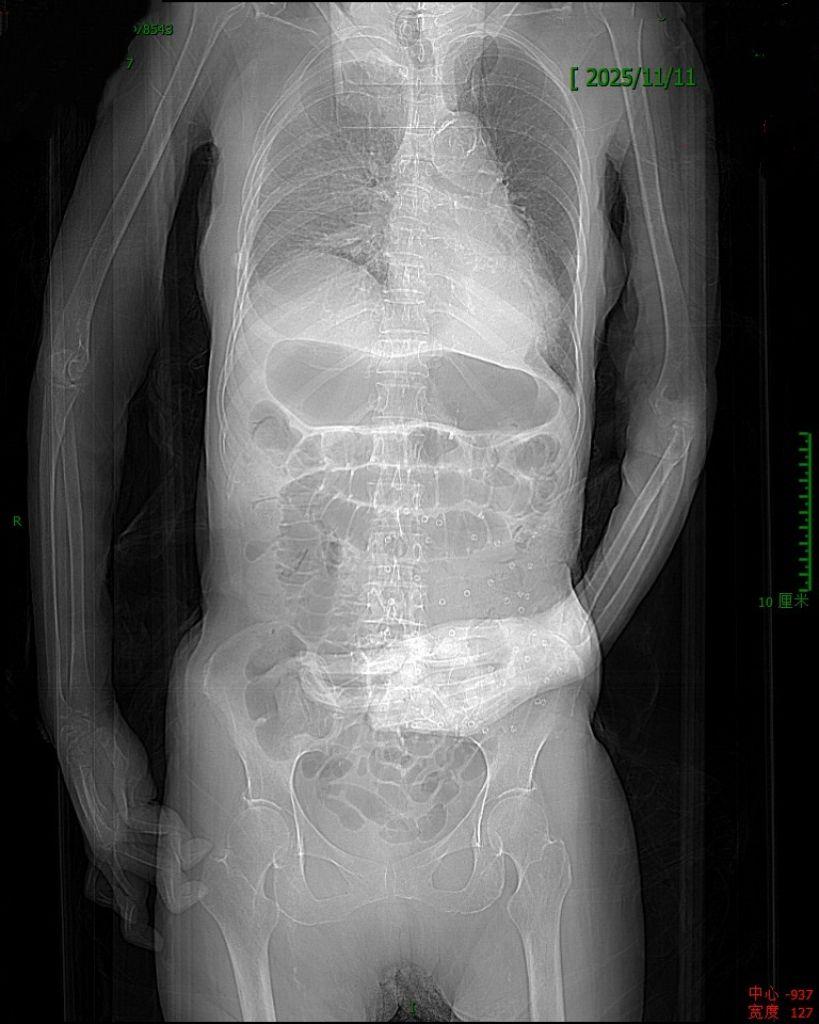

小肠梗阻,有时候略显隐蔽的腹痛